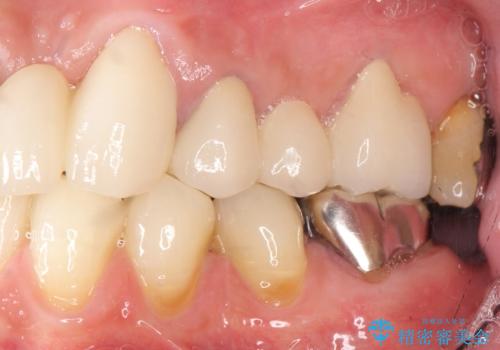

歯の牽引後、ブリッジの仮歯で保定しながら歯肉・骨の治癒を待ったのち、ブリッジによる補綴を行いました。

根の長さが短くなるためブリッジの支台歯としては弱いこと、長期的予後は不明なことをご理解頂いた上で治療を行いました。

根管治療はご希望されず行っておりません。

左上2欠損部の軟組織のボリュームが少なくポンティック部に食渣がたまりやすい歯肉形態であったため、歯槽堤増大術も提案しましたがご希望されませんでした。